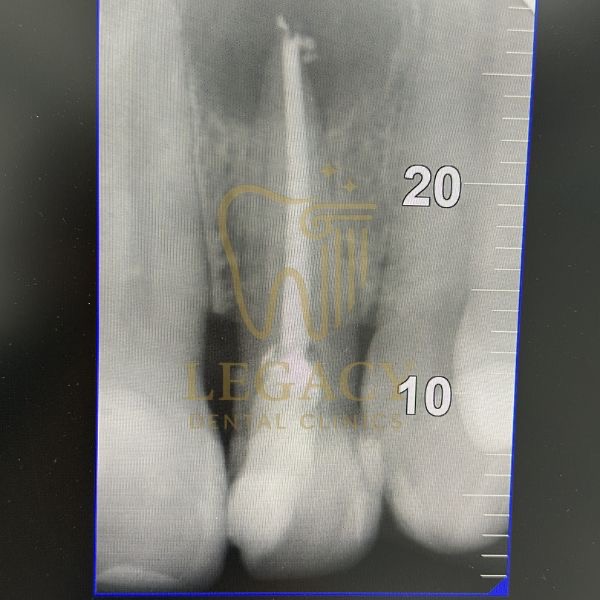

حالة زراعة فورية لسن أمامي - د.عمر نافوخ